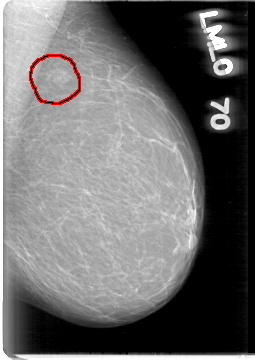

D_4003_1.RIGHT_MLO

LEFT_MLO LINES 5386 PIXELS_PER_LINE 3811 BITS_PER_PIXEL 12 RESOLUTION 43.5 OVERLAY

FILE: D_4003_1.LEFT_MLO.OVERLAY

TOTAL_ABNORMALITIES 1

ABNORMALITY 1

LESION_TYPE MASS SHAPE IRREGULAR MARGINS OBSCURED

ASSESSMENT 0

SUBTLETY 4

PATHOLOGY BENIGN

TOTAL_OUTLINES 1

BOUNDARY